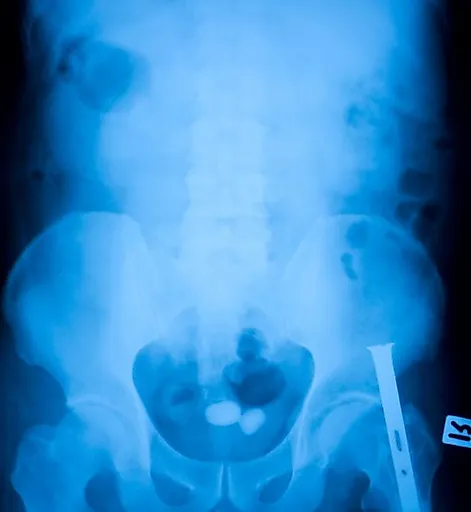

Мочекаменной болезнью называют патологию, характеризующуюся формированием конкрементов в органах мочевыделительной системы. Чаще всего камни образуются в почках, мочеточниках и мочевом пузыре. Клинические проявления недуга зависят от размера конкрементов, наличия воспалительного процесса и других факторов, однако к наиболее распространенным осложнениям болезни врачи относят закупорку мочеточника, невыносимую боль и повреждение слизистых оболочек.